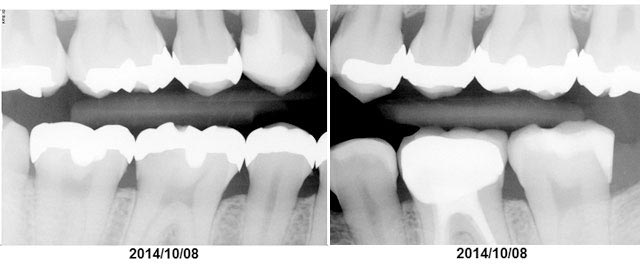

2.レントゲン

英語ではX-rayと呼ぶ方が一般的です。左右1枚ずつのレントゲンを撮ります。歯と歯の間に虫歯や歯石が無いか、歯を支えている骨が痩せていないか、詰め物や銀歯の状態は大丈夫か、などを知ることができます。

現在はレントゲン技術も進んでおり、デジタルX-rayを使用している歯科医院も増えてきました。

従来のフィルム式に比べると、デジタルの場合はそのままパソコンにイメージが送られるので、現像する時間を待つ必要がありません。さらに、放射線被爆量がフィルムの1/4~1/10に抑えられます。飛行機でNZ日本間を移動するよりはるかに被爆量が低いです。